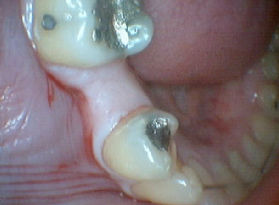

Bruxir Crown, Fractured Alloy